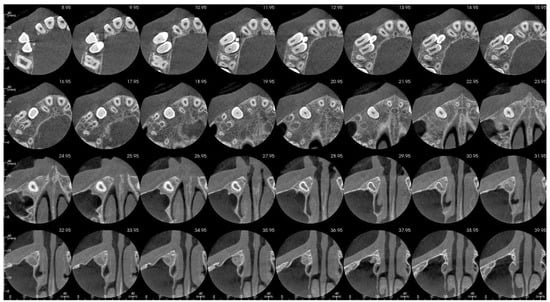

That finding necessitated further diagnostics with CBCT (Figure 4, Figure 5, Figure 6 and Figure 7). A 3D radiograph confirmed a round, well-demarcated, noninflammatory cyst-like lesion extending from Teeth 11 to 15.

Figure 4.

CBCT before treatment—sagittal view.

A hypodense focus representing a loss of osseous tissue surrounded the crown of the displaced upper right permanent canine. The unerupted first and second premolars were dislocated and rotated, and Tooth 12 also presented mesiorotation and mesioinclination. The teeth involved in the lesion had open apices and no sign of root resorption. The alveolar bone was deformed, especially in the vestibulopalatal dimension, with a noticeable displacement of the medial interior wall of the right maxillary sinus.